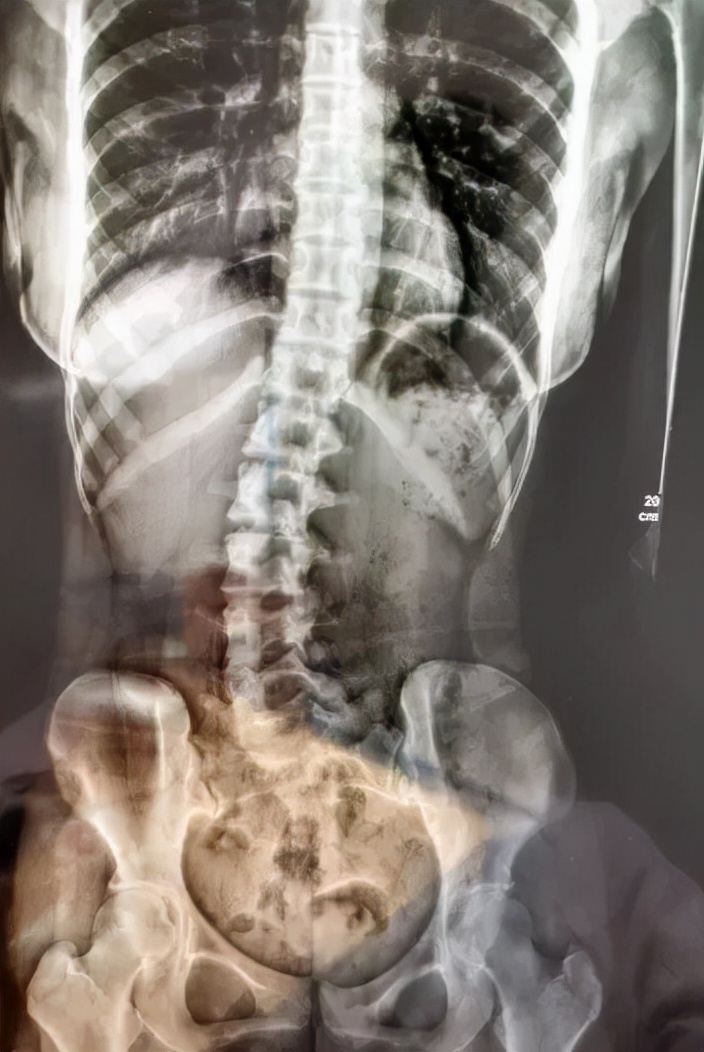

新闻中,广州18岁少女小邹,因腰痛、脖子酸等症状到医院就诊,检查发现脊柱严重侧弯。医生详细问诊得知,小邹习惯侧睡,且长期侧向右边。

广州医科大学附属第三医院中医科主任医师胥海斌表示:“小邹长期不正确睡姿,使正常的脊柱逐渐失衡,从而发生侧弯。”